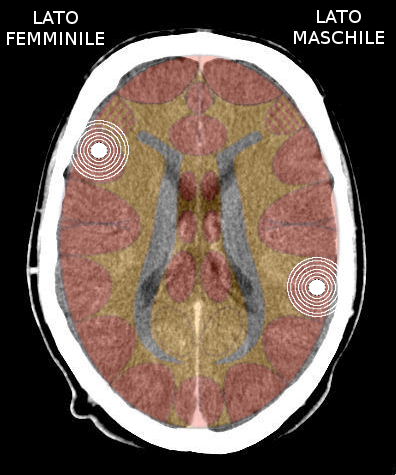

- Requisiti: Si è in costellazione schizofrenica quando due attivazioni colpiscono i due emisferi cerebrali di uno stesso livello:

- le due emiparti del tronco cerebrale;

- i due emisferi cerebellari;

- i due emisferi cerebrali (midollo e/o corteccia).

- NON È COSTELLAZIONE quando due attivazioni interessano due livelli cerebrali differenti, anche se occupano i due emisferi.